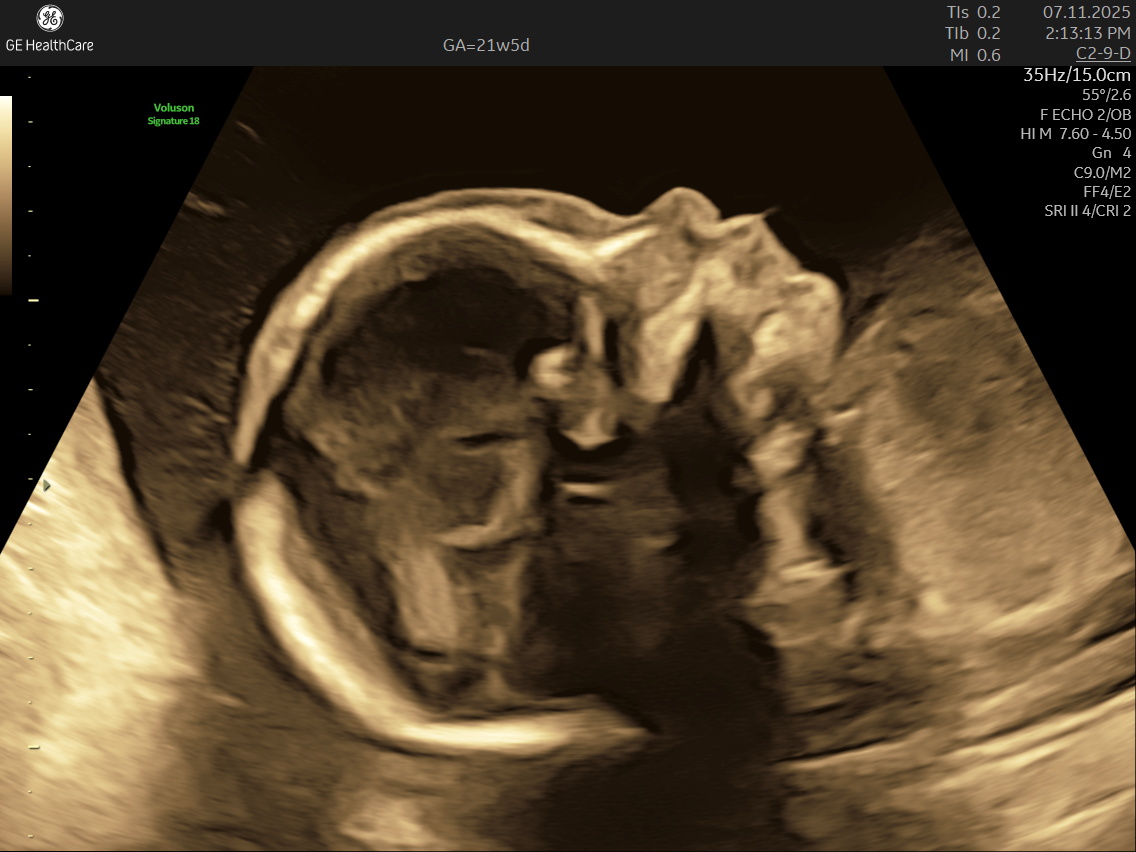

IMAGE GALLERY

If you’re expecting a baby, the Detailed Anatomy Scan —also known as the Fetal Anomaly Scan — is one of the most important checks you’ll have during pregnancy. Usually done between 18 and 22 weeks, this ultrasound is performed by highly trained fetal medicine specialists at NESA Institute of Fetal Medicine. The scan provides a close-up look at your baby’s overall development and helps to make sure everything is progressing as it should.

During this scan, the MFM specialist carries out a detailed examination of your baby’s body, checking their vital organs, spine, head, heart, limbs, and more. The aim is to confirm that your baby’s growth is on track and can identify various structural abnormalities and potential complications early, so that appropriate steps can be taken early.

• Head and Brain: The scan looks at the baby’s skull shape and examines the brain’s key areas, checks the structure and growth of the brain and skull, ensuring everything is forming correctly.